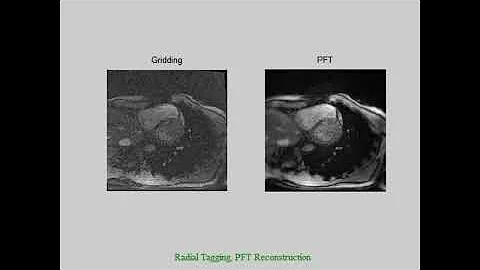

PFT vs Conventional reconstruction

Acquisition/Reco... in the fully polar Coordinates can significantly ...

PFT reconstruction - ZooMRIn

Advantages of PFT to gridding for MRI reconstruction are depicted in a...